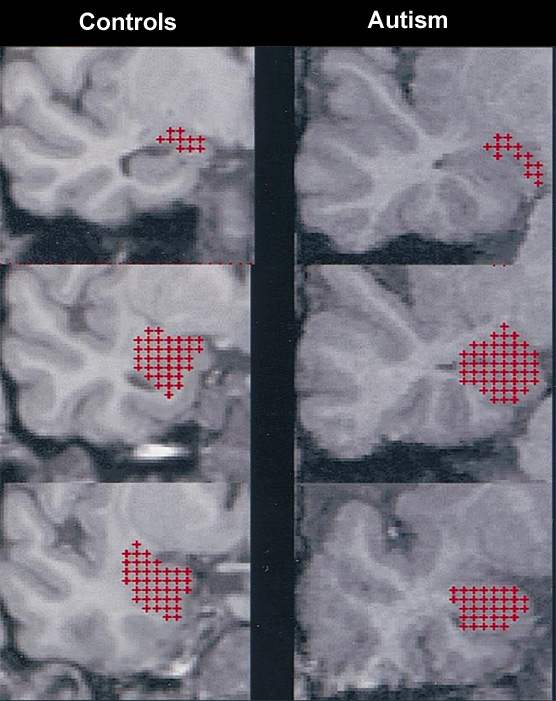

Modified from Fig. 2 (Howard et al., 2000). Volume estimation of the amygdala by the stereological point counting method. Section area estimation of posterior, middle, and anterior amygdala sections, using a regular array of test points. Section areas are increased in autism compared to controls.